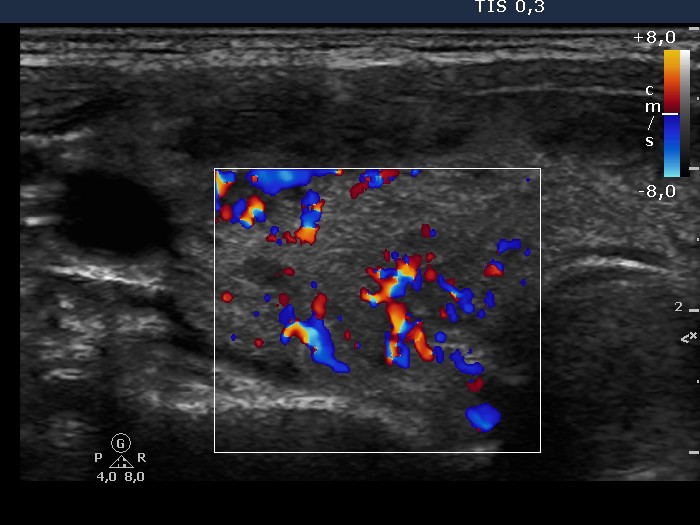

Follow-up investigation 32 months after first visit (ultrasonographic picture 3)

Patient 14 months after discontinuation of thyrostatic therapy in hyperthyroid state

Right lobe, transverse scan, color Doppler mode. The vascularization is increased.